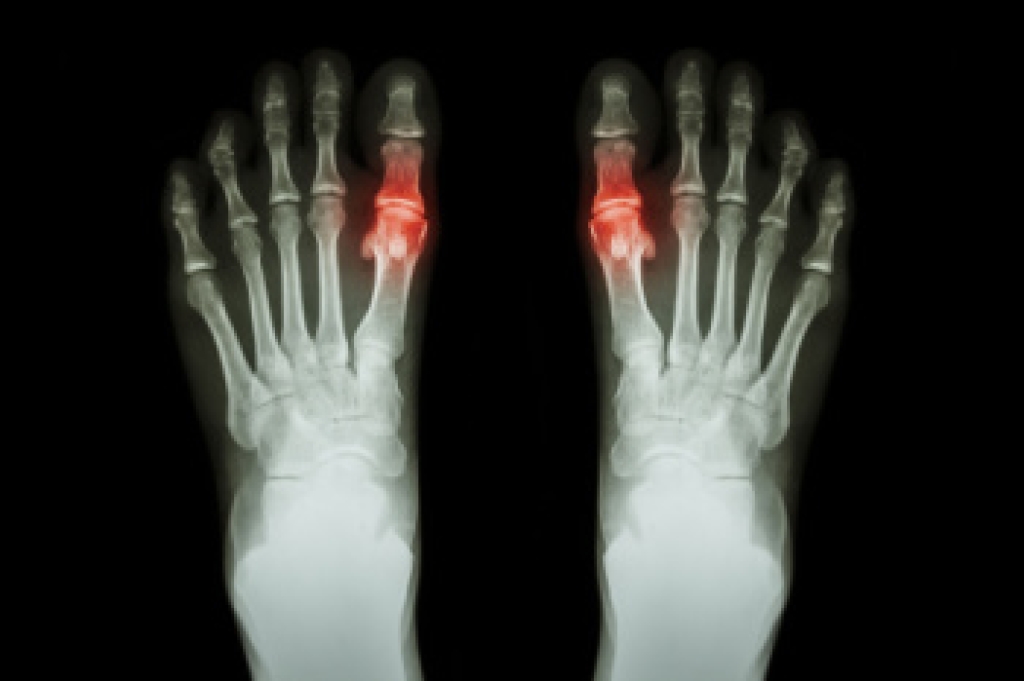

What to Do About Gout

Gout is a type of arthritis caused by the accumulation of uric acid crystals in the joints, often affecting the feet, particularly the big toe. It leads to sudden, severe pain, in addition to redness and swelling. Gout predominantly affects middle-aged men and postmenopausal women, especially those with a diet high in purines, a substance found in red meat and alcohol. The condition is often diagnosed through blood tests measuring uric acid levels and joint fluid analysis to detect urate crystals. Treatment focuses on reducing pain and inflammation with nonsteroidal anti-inflammatory drugs, corticosteroids, or colchicine. Long-term management includes medications like allopurinol or febuxostat to lower uric acid levels. For foot-specific care, patients may elevate the affected foot and wear comfortable, supportive footwear to alleviate symptoms and prevent flare-ups. Preventing gout involves maintaining a healthy diet, staying hydrated, and avoiding foods high in purines. Regular exercise and weight management are also critical. If you have gout that is negatively impacting your feet, it is suggested that you consult a podiatrist for specialized care and tailored advice.

What Is Gout?

Gout is a type of arthritis caused by a buildup of uric acid in the bloodstream. It often develops in the foot, especially the big toe area, although it can manifest in other parts of the body as well. Gout can make walking and standing very painful and is especially common in diabetics and the obese.

People typically get gout because of a poor diet. Genetic predisposition is also a factor. The children of parents who have had gout frequently have a chance of developing it themselves.

Gout can easily be identified by redness and inflammation of the big toe and the surrounding areas of the foot. Other symptoms include extreme fatigue, joint pain, and running high fevers. Sometimes corticosteroid drugs can be prescribed to treat gout, but the best way to combat this disease is to get more exercise and eat a better diet.